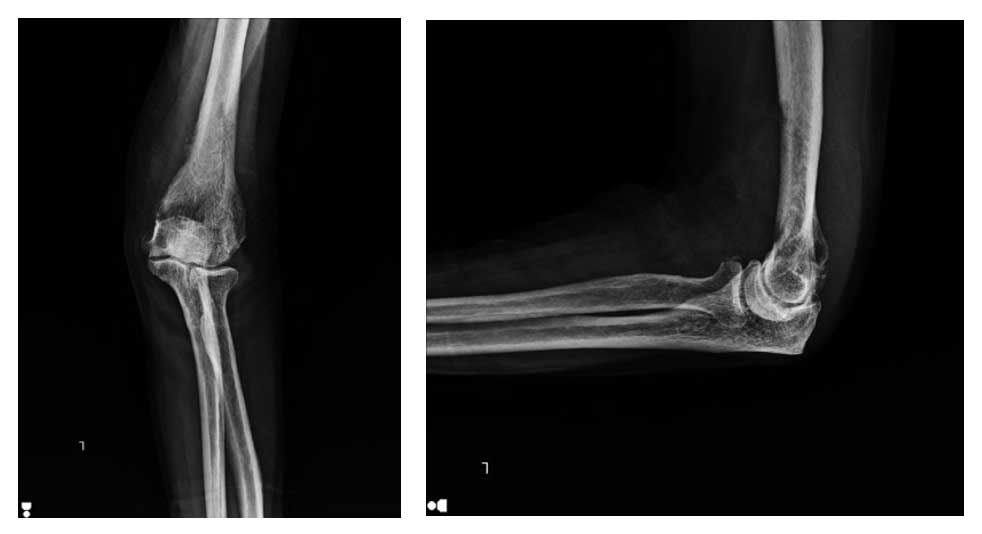

Ameliyat Öncesi: Röntgende humerus alt uçta düzensizlik görülmekte.